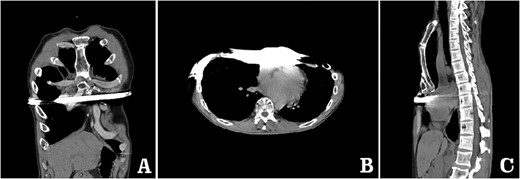

examination showed that the anterior chest wall was sunken and uneven in the middle, and two scars were visible on the lateral chest wall (Fig. 1). The preoperative imaging examination showed that there was a steel bar in the chest wall, and the anterior chest wall was depressed. The lower part of the sternum was broken, with its distal end was supported up by the steel bar. The lower end of the sternum was located deep beneath the steel bar, and the heart was obviously compressed (Figs 2–5). The operation was performed under general anesthesia. Incisions were made in the middle of the depression and two sides of chest wall. After the steel bar was taken out, the adhesion behind the sternum was separated through the median incision. Wung procedure was performed with two steel bars to support the depressed lower part of sternum [4], and then, the third steel bar was used to perform Wenlin procedure to flatten the protrusion part of the rib arch [5, 6] (Figs 6 and 7). During the two procedures, Wang technique was used to fix all the steel bars [7]. After the two procedures were completed, drainage tubes were placed in bilateral thoracic cavities and median surgical field, and the incision was closed to end the operation (Fig. 8). The operation time was 90 min, and the operation was smooth without any complications. The appearance of chest wall returned to normal after the operation, and imaging examination showed that the position of steel bars was satisfactory (Figs 8 and 9). The patient was discharged 7 days after operation.

X-ray examination before operation. (A) Posteroanterior radiograph; and (B) lateral radiograph.